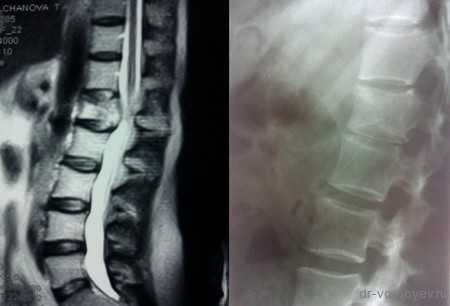

На данных томограммах представлен нестабильный перелом тела Тн12 позвонка

Первым этапом выполнена ламинэктомия с транспедикулярной фиксацией китайской системой, а затем проведена корпорэктомия, корпородез аутокостью и тораколюмбальной пластиной китайского производства.